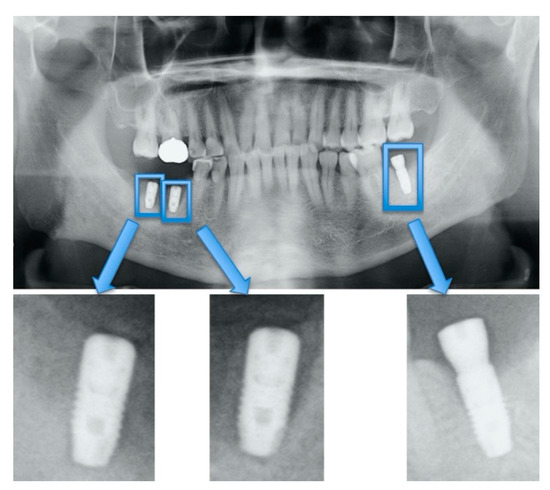

2.4. Data Preprocessing

2.5. Convolutional Neural Network